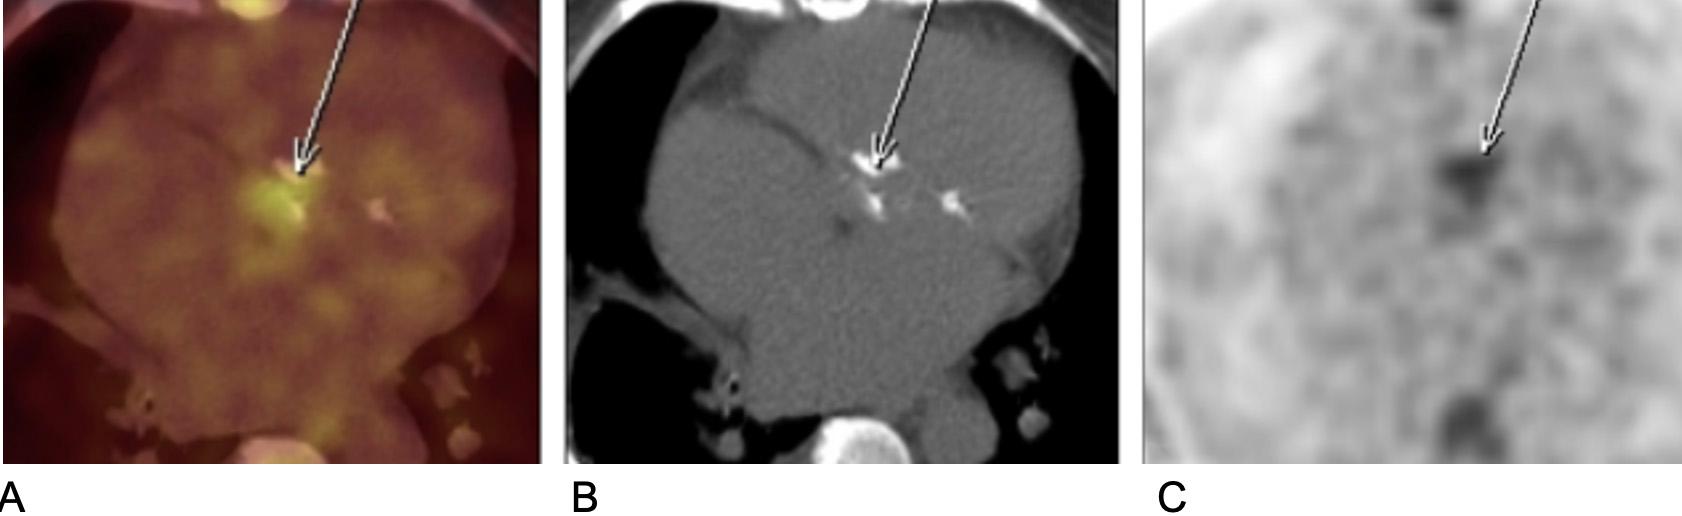

Segundo a sub-análise publicada recentemente no JACC Adv sobre o estudo DISCHARGE, sim1.Esse ensaio clínico se propôs a avaliar se a angiotomografia de coronárias seria superior ao cateterismo na ava…